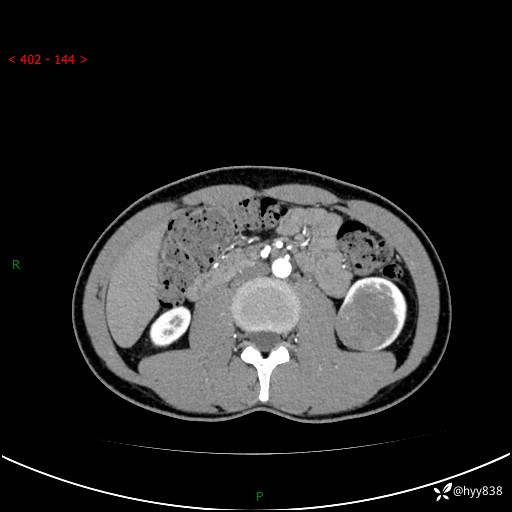

现病史:患者昨日中午进食后出现明显腹痛,腹泻,在我院急诊科行补液及对症治疗,双肾输尿管彩超提示左肾占位(5.2*4.3cm),平素无明显腰痛,无再发肉眼血尿等情况,现为求处理左肾占位,遂来我院,门诊以左肾占位收治入院。 患者起病以来,精神、食欲、睡眠尚可,大便可,小便如上,体力体重无明显下降。

双肾CT平扫+增强(三期)